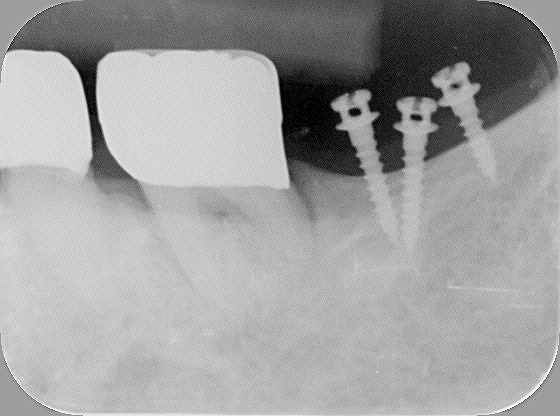

エックス線で見ますと、もっとリアル感が増します。

この方は上記の③の理由で、矯正を始められました。固定装置の補強用に三本のミニインプラントを入れました。

小さくても、力持ちで以外に動きませんので、治療も早く終われます

間もなく、治療が終了しますので、その時にまたこの方の結果を紹介したいとおもいます。